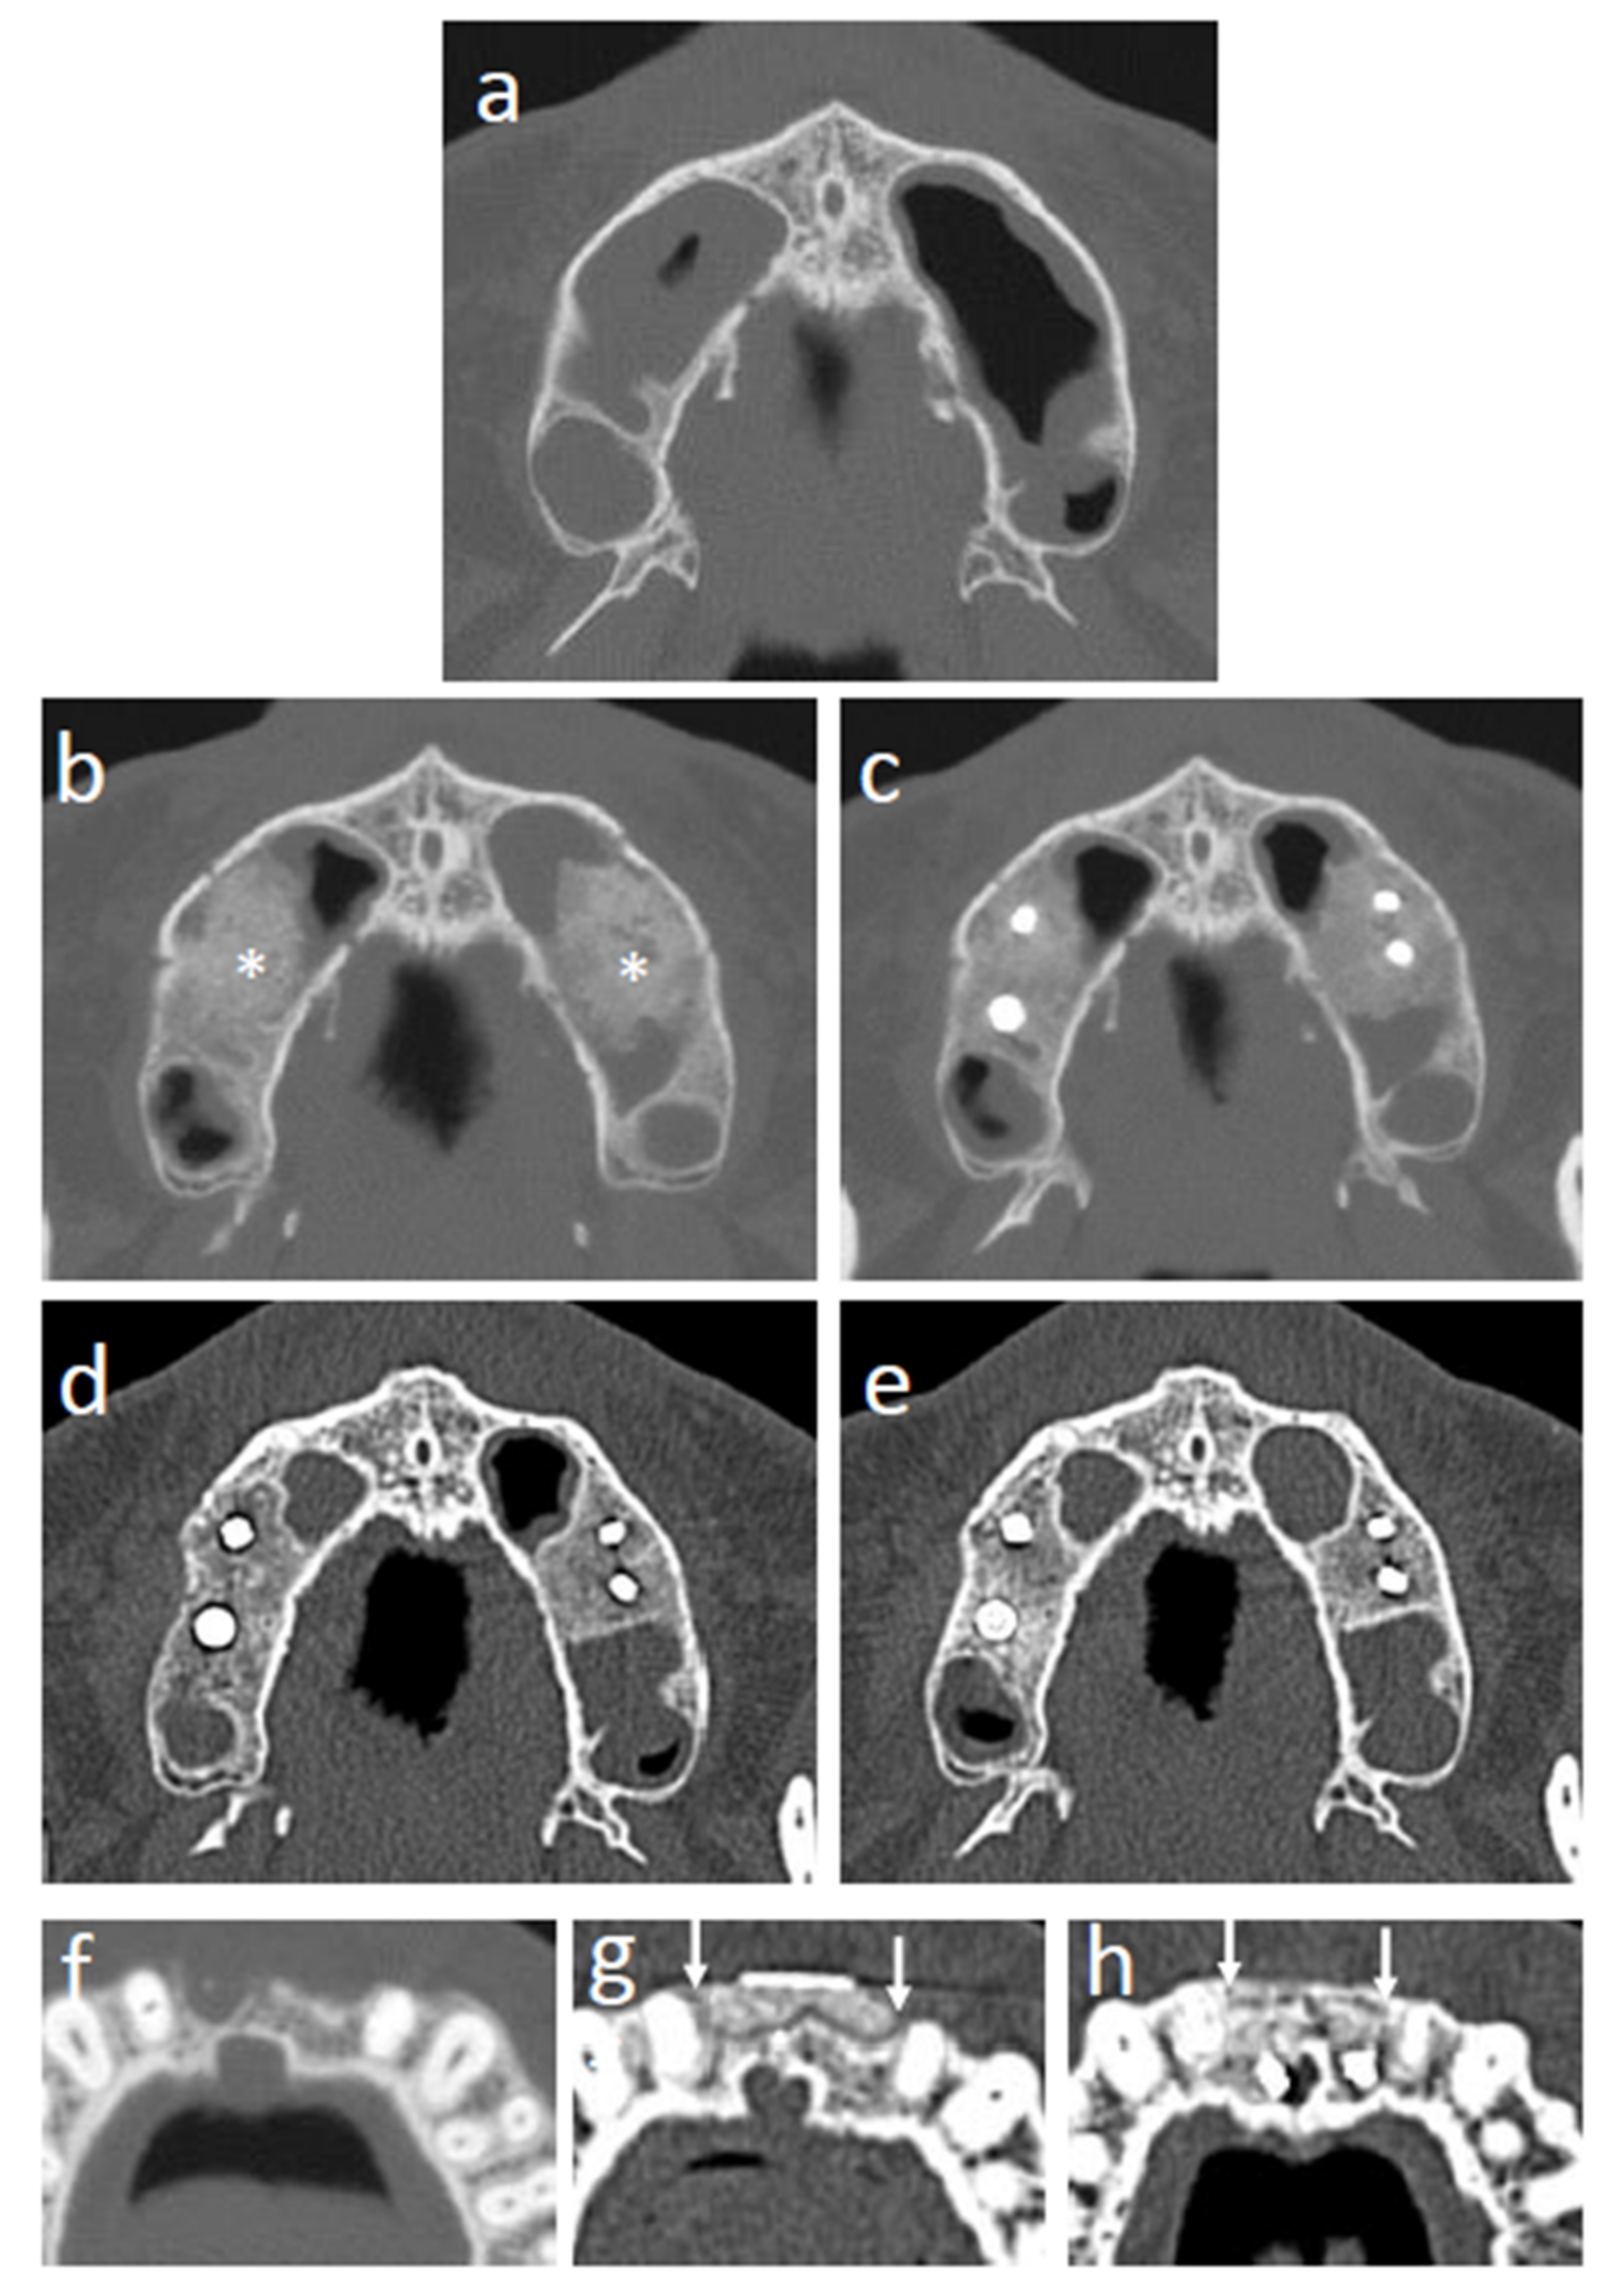

3.7. CT Images

The CT images of representative cases are shown in Figure 6. Sinus floor augmentation was performed in cases with bone resorption at upper molar region (Figure 6a). In the cases of sinus floor augmentation, the transplanted tissue-engineered bone initially showed an irregular margin, and the β-TCP granules were still recognizable at 3 months (Figure 6b). After 6 months, β-TCP granules were mostly degraded, but the trabecular structure was not regenerated (Figure 6c). After 12 months, the trabecular structure gradually formed, and the border between the regenerated and original existing bone became unclear (Figure 6d). At 24 months after transplantation, the trabecular structure was mostly regenerated, and the regenerated bone was hard to distinguish from the surrounding existing bone (Figure 6e). Alveolar ridge augmentation with tissue-engineered bone was performed in cases with narrow alveolar ridges (Figure 6f). At 3 months, the border between the transplanted tissue-engineered bone and the surrounding existing bone was clear and β-TCP granules remained, as shown in the sinus floor augmentation cases (Figure 6g). At 24 months after transplantation, the border between the regenerated bone and existing bone became unclear (Figure 6h).

Figure 6. CT images of regenerating sites. (a) Sinus floor augmentation case before transplantation. (b) Sinus floor augmentation case at 3 months after transplantation (* shows the transplanted tissue-engineered bone). (c) Sinus floor augmentation case at 6 months after transplantation. (d) Sinus floor augmentation case at 12 months after transplantation. (e) Sinus floor augmentation case at 24 months after transplantation. (f) Alveolar ridge augmentation case before transplantation. (g) Alveolar ridge augmentation case at 3 months after transplantation (white arrows indicate the area of transplanted tissue-engineered bone). (h) Alveolar ridge augmentation case at 24 months after transplantation (white arrows indicate the area of transplanted tissue-engineered bone).